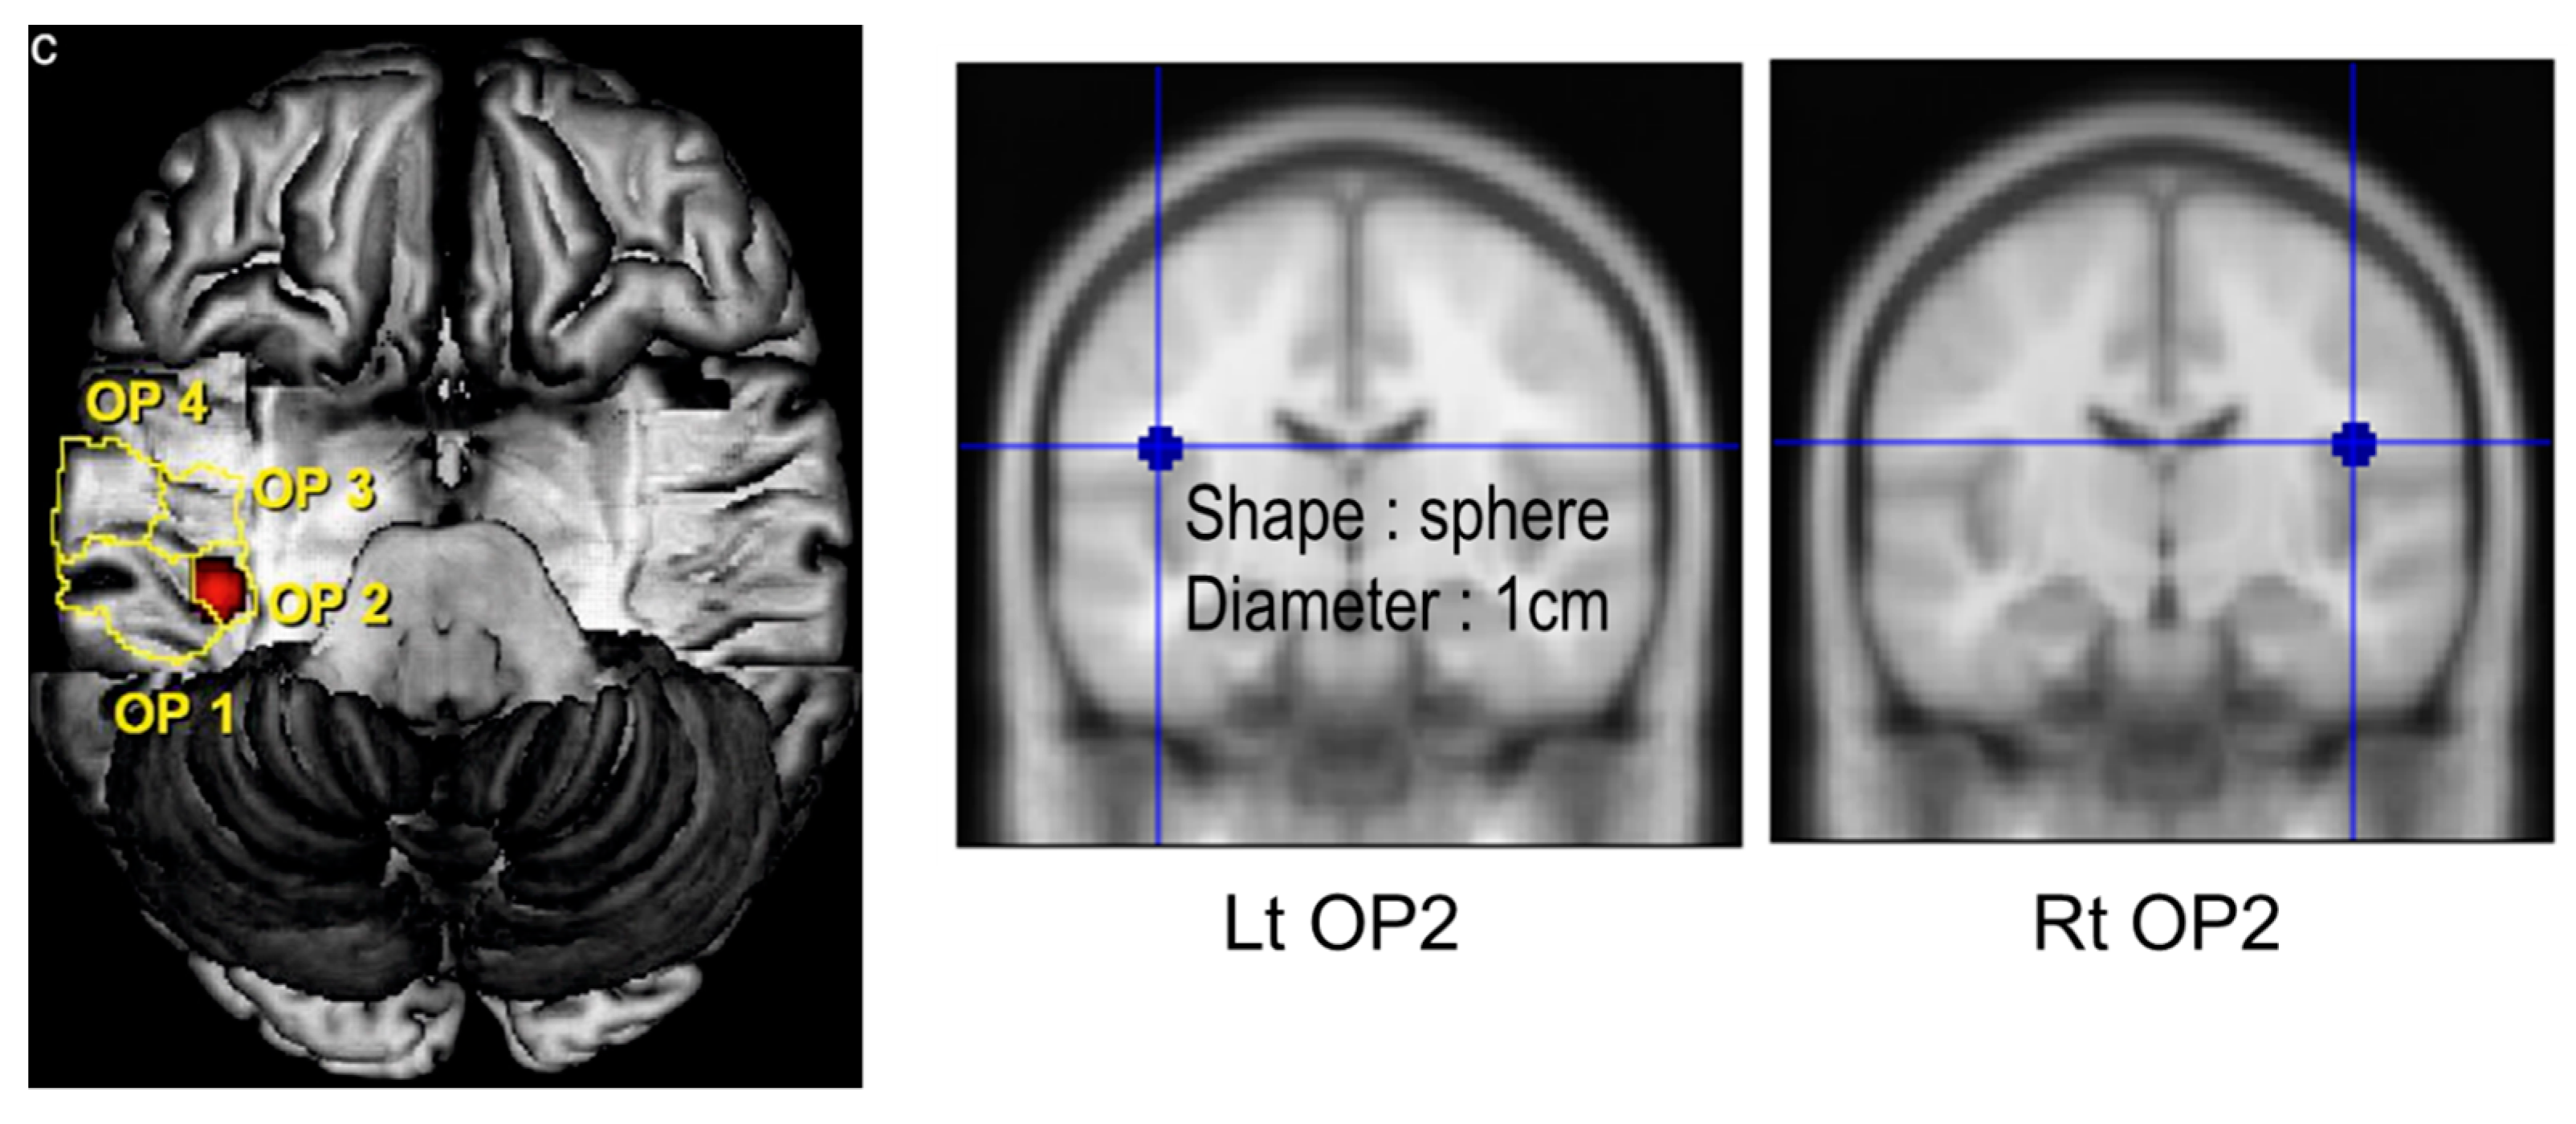

| Parietal operculum 2 | |||

| GMV | 0.366 ± 0.071 | 0.499 ± 0.066 | <0.001 * |

| WMV | 0.332 ± 0.034 | 0.248 ± 0.053 | <0.001 * |